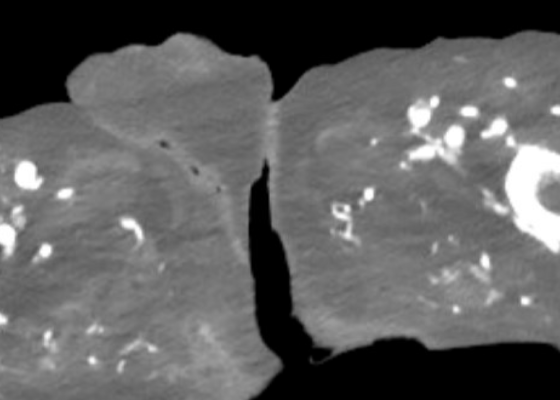

A Case Report of an Atypical Presentation of Fournier’s Gangrene

DOI: https://doi.org/10.5070/M5.52203A computed tomography (CT) scan of the abdomen and pelvis was significant for scrotal fluid and punctate gas locules (red arrow) without discrete evidence of invasion into the adjacent soft tissues, suspicious for Fournier’s gangrene. There was also fluid collection centered around the seminal vesicles suggestive of an abscess.